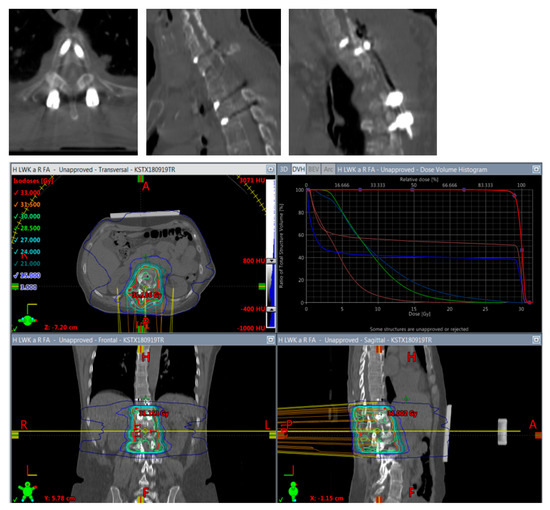

Figure 5.

Planning of postoperative radiotherapy: titan. Planning of conventional radiotherapy (30 á 3 Gy) of the vertebral body plus all instrumented levels.